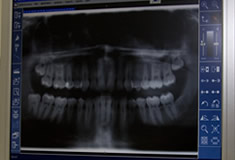

Zahnärztliche Chirurgie

Wir führen chirurgische Eingriffe, wie z.B. Zahnentfernung, einfache Wurzelspitzenresektionen, Weisheitszahnentfernung und erweiterte Parodontitistherapie in unserer Praxis normalerweise selbst durch.